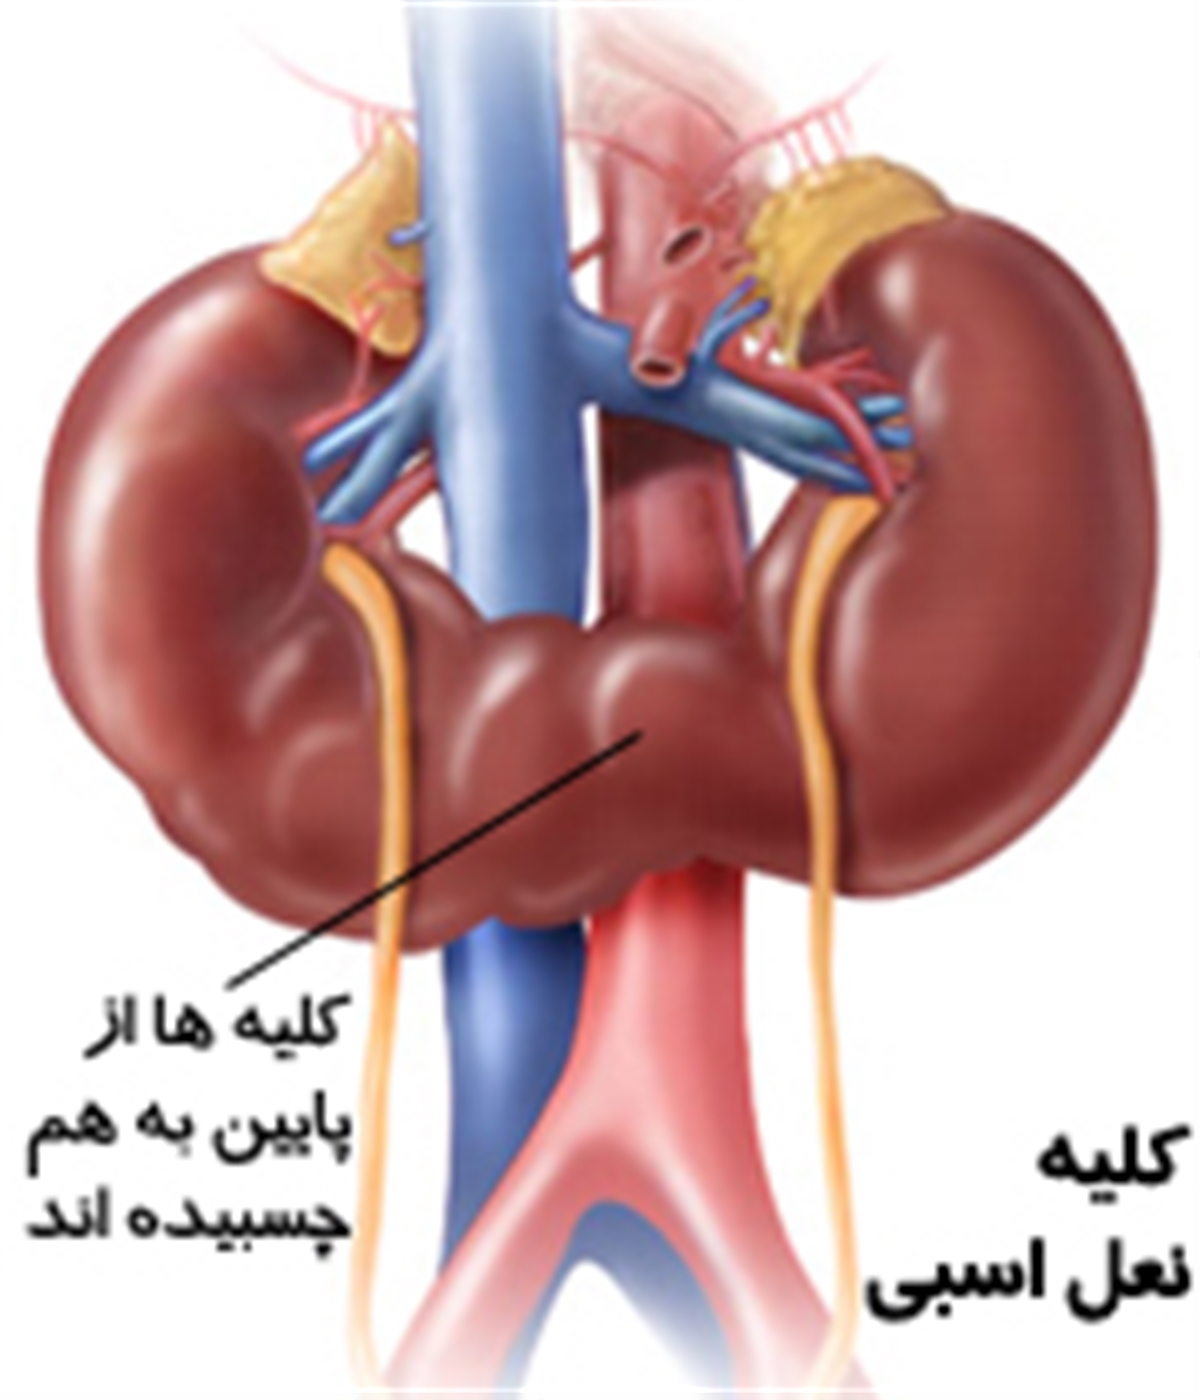

عکس کلیه در بدن. اگر پشت یا پهلوی شما آسیب ببیند مثل برخورد ضربه ممکن است فکر کنید که کلیه هایتان درد می کنند. مقدار و نسبت ترکیب این اخلاط در بدن هر شخصی و در اندامهای. کلیه گ رده ها1 از اندام های درونی بدن انسان به صورت یک جفت عضو لوبیایی شکل در طرفین ستون فقرات روی جدار پشتی شکم و بیرون از حفره صفاق قرار دارند. ک لیه ق لوه میز یا گ رده یکی از اندام های درونی بدن انسان و برخی دیگر از جانداران است.

کلسیم و فسفر که برای تشکلی استخوان لازمند کمک می کنند مواد. کلیه ها با تولید ادارد در دفع مواد زاید تعادل الکترولیتی تنظیم هورمونی تنظیم فشار خون و هوموستازگلوکز نقش دارند. آناتومی کلیه انسان در بدن انسان به این شکل است که کلیه ها دو عضو لوبیایی شکل در دستگاه ادراری بوده و به دفع مواد زائد به صورت ادرار کمک می کنند. یکی از مهم ترین وظایفی که کلیه ها در بدن بر عهده دارند پاک کردن و تصفیه خون از زباله هاست.